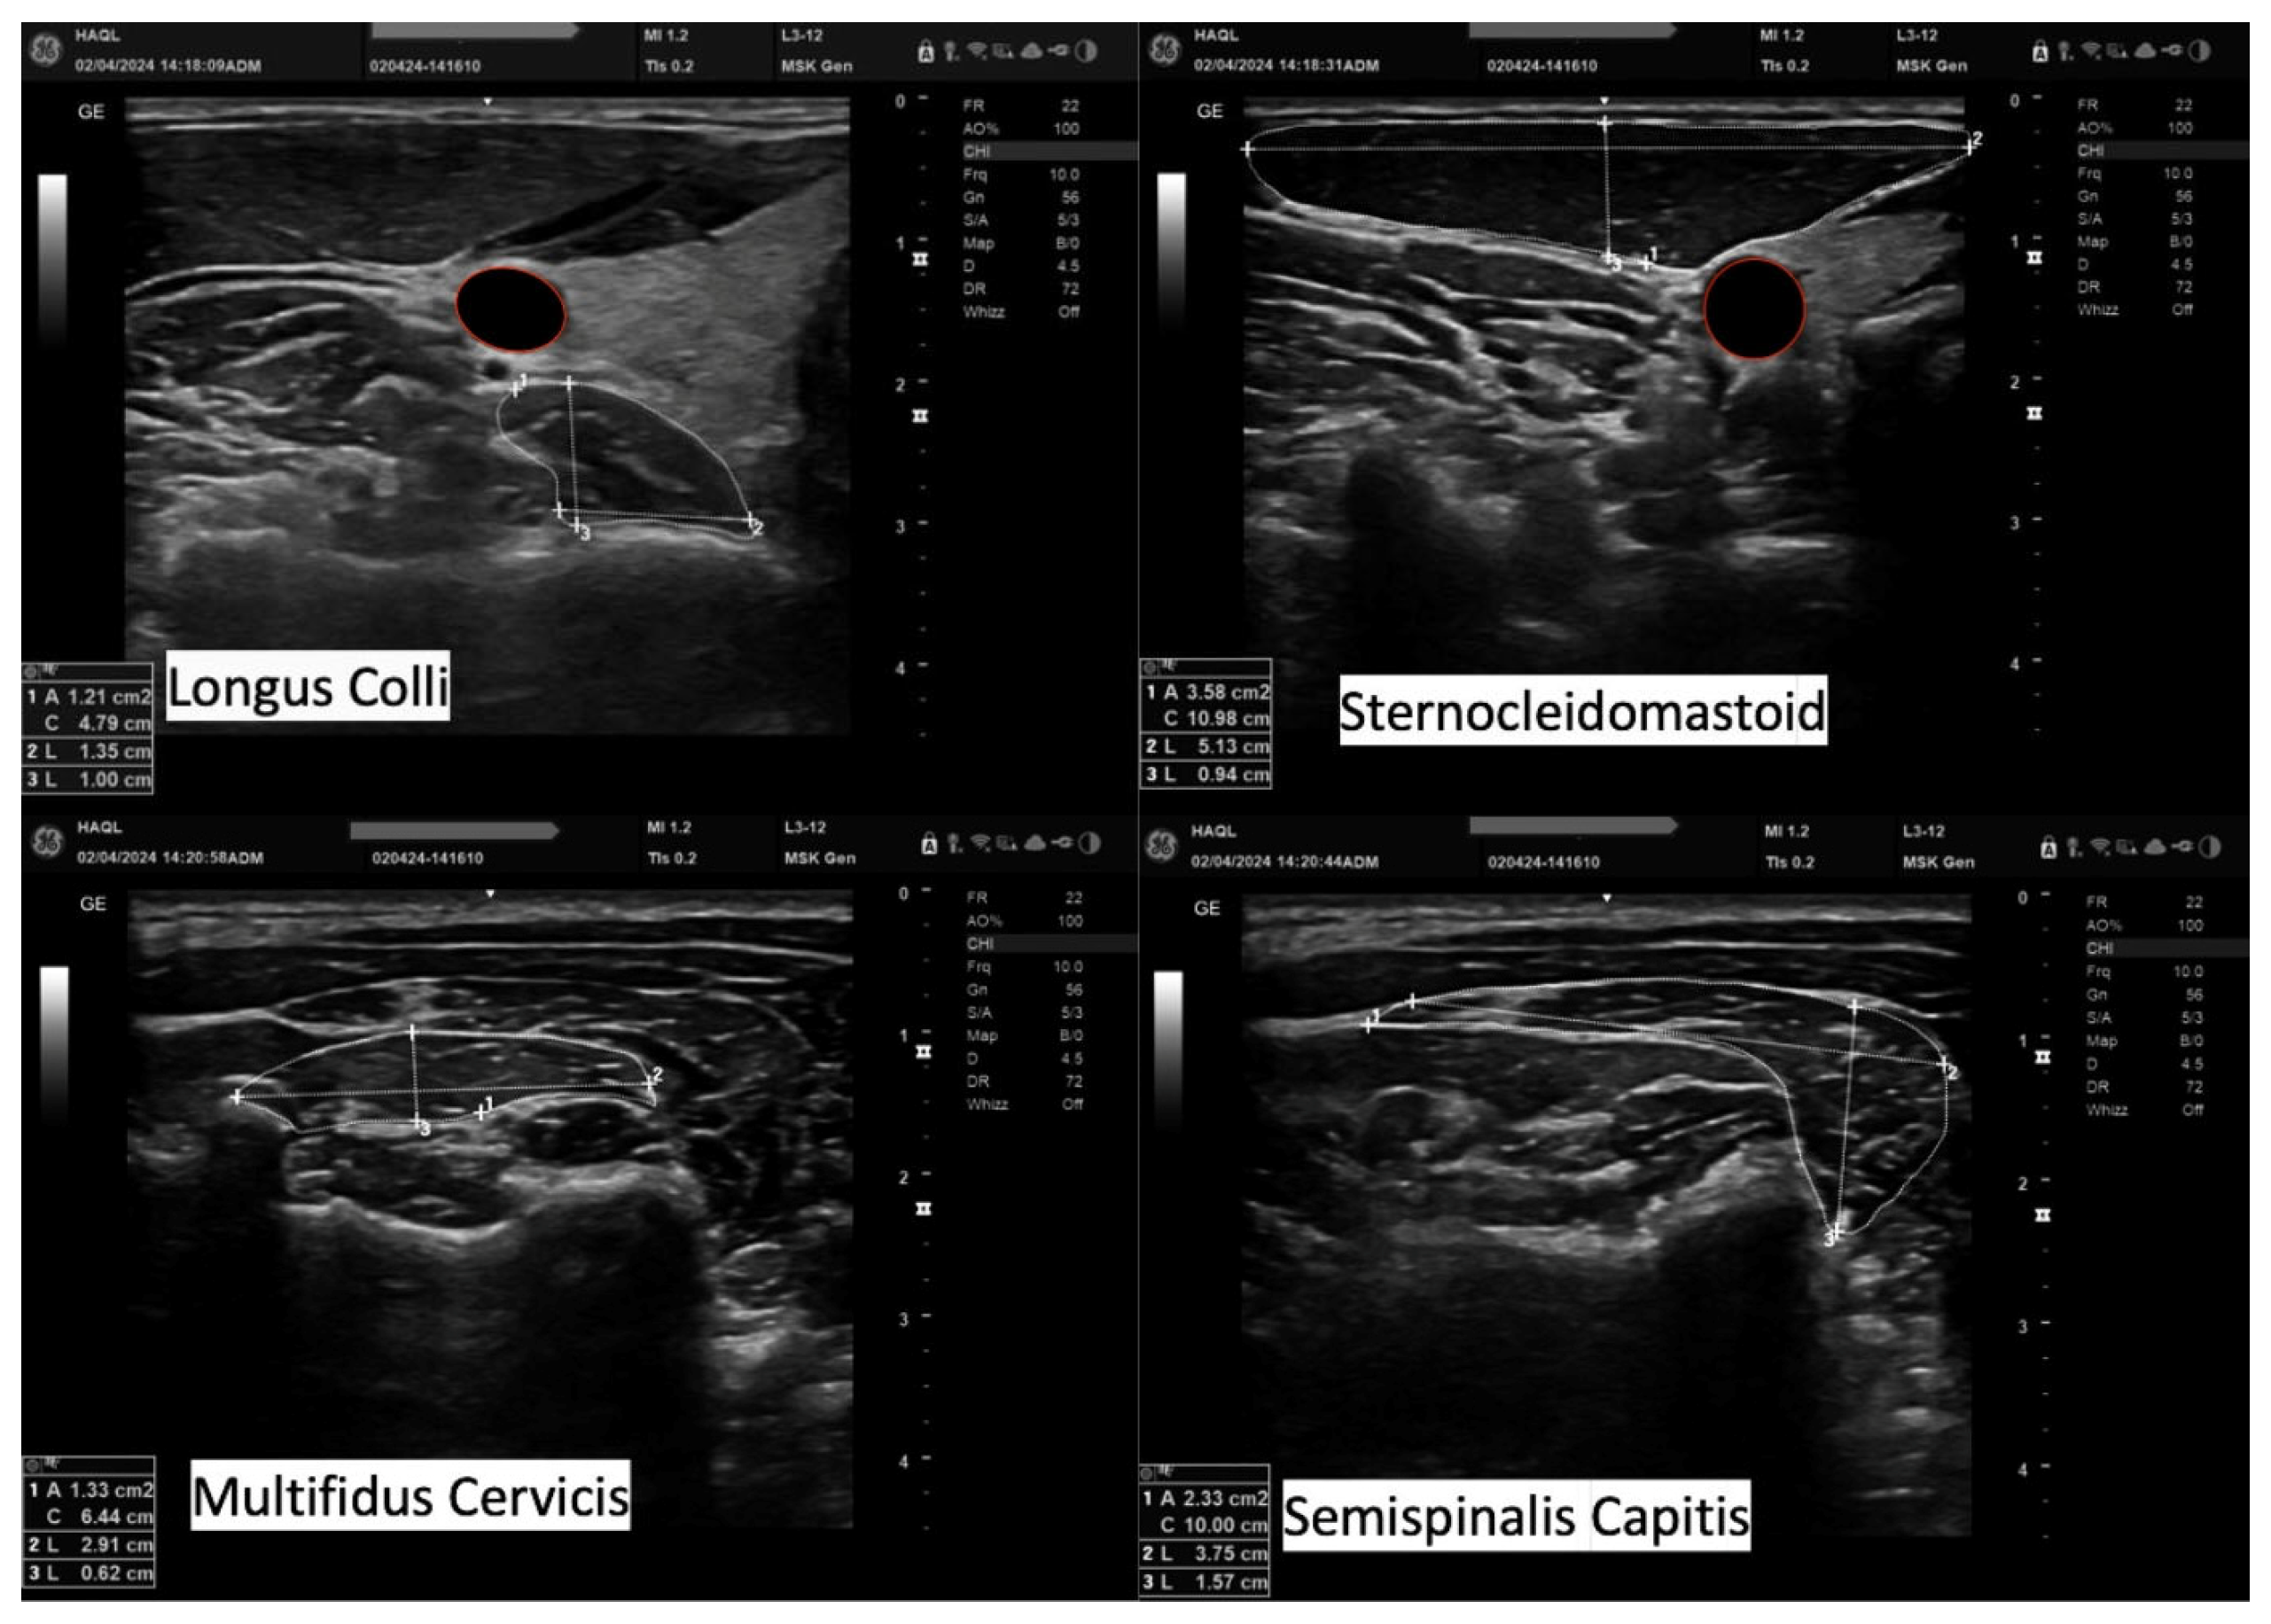

After completing the data collection phase, all ultrasound images were stored and processed by the same examiner approximately one month later. At that time, the datasets were anonymized and coded to reduce observer bias during data processing. The CSA of each muscle was captured by tracing the perimeter of the muscle tissue carefully, excluding the surrounding fascial layers and connective tissues. The LD measurements were taken at their greatest visible distance, with the lines aligned, whereas APD was measured in the same way so that a 90-degree angle was formed between them (Figure 3).

Figure 3.

Data processing of the ultrasonographic measurements. Cross-sectional area, anteroposterior dimension, and lateral dimension of the Longus Colli, Sternocleidomastoid, Multifidus Cervicis, and Semispinalis Capitis.